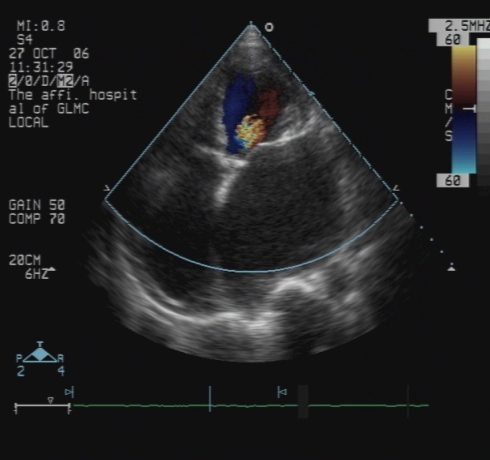

心脏彩超:

● RVOT:33mm,AOV:30mm,LAS:72mm,RAS:65mm,LAD:61mm,LVPWD:10mm,IVS:10mm,RVD:22mm,EF:0.67,FS:30%。全心增大,主动脉瓣反射增强,余瓣膜柔软不厚,闭合良好,室间隔与左室后壁不厚,呈逆向运动。房室间隔连续性完整。

● 彩色多普勒示:二尖瓣区及主动脉瓣区及肺动脉瓣区可见轻度反流,二尖瓣最大反流速度3.88m/s,主动脉瓣区最大反流速度2.56m/s,PG26.2mmHg,据三尖瓣反流束估测肺动脉收缩压为47mmHg。房室水平未见分流。

提示:全心大

二瓣及主动脉瓣关闭不全并轻度反流

轻-中度肺动脉高压